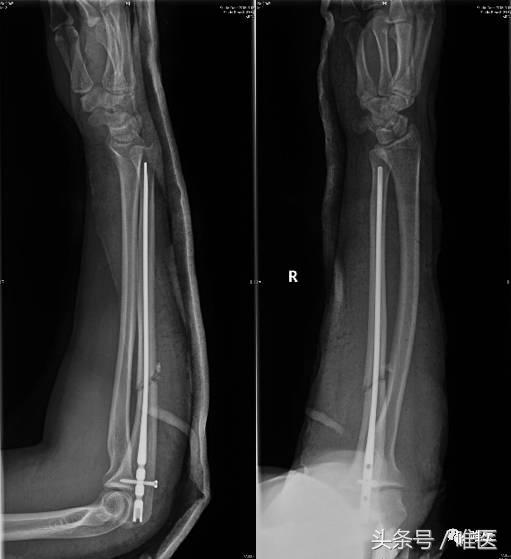

▣ 行闭合复位Acumed髓内钉固定